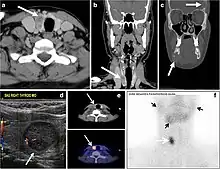

Fig. 7. A 51-year-old female patient post total thyroidectomy for PTC with elevated thyroglobulin measurement. an Axial non-enhanced CT scan of the neck at the level of the thyroid bed demonstrates a well-defined, rounded, homogenously dense soft tissue situated between the trachea and left internal jugular vein (white arrow). b Transverse ultrasound image of the neck demonstrates a well-defined, homogeneous, hypoechoic soft tissue nodule measuring 6 mm (white arrow) with no detected micro-calcifications. Biopsy showed a predominantly residual normal thyroid tissue with micro-foci of PTC.[1]

Fig. 8. A 48-year-old male patient post total thyroidectomy with PTC recurrence. a Transverse greyscale ultrasound of the neck demonstrates a left thyroid bed heterogeneous, predominantly hypoechoic irregular lesion with calcifications (white arrow). b A spot image of iodine 123 total body scan of the neck demonstrate a focus of abnormal radiotracer uptake at the left thyroid bed (Black arrows) between the annotated markers. c Enhanced axial CT scan of the neck demonstrates an enhancing large left thyroid bed mass (white arrow) with no calcifications. The lesion exerts a mass effect on the oesophagus (black arrow) and is inseparable from the trachea.[1]

Fig. 9. A 58-year-old male patient with persistence PTC at thyroid bed with hypervascular nodal metastasis. a–c Transverse greyscale and colour Doppler neck ultrasound demonstrate hypoehoic soft tissue in the left thyroid bed (white arrow in a). There are a heterogeneous enlarged lymph nodes at level 2 and 3 with markedly increased vascularity (white arrow in b and c). d–f Enhanced axial CT images of the neck demonstrate a 2.7 × 1.4 cm hypodense soft tissue lesion anterior to the left carotid sheath (white arrow). There are left-sided enhancing abnormal and enlarged lymph nodes at cervical level 2 and 3 (black arrows).[1]